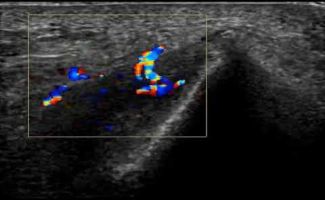

Η τεχνική PRP περιλαμβάνει τη λήψη μίας μικρής ποσότητας αίματος του ασθενούς, το οποίο φυγοκεντρείται ώστε να διαχωριστεί το πλάσμα που είναι πλούσιο σε αιμοπετάλια. Το προκύπτον πλάσμα εγχέεται, με την καθοδήγηση υπερήχου, στο σημείο της βλάβης.

Η καθοδήγηση υπερήχου κατά την ενέσιμη θεραπεία PRP αποτελεί κρίσιμο παράγοντα για την ακρίβεια και ασφάλεια της διαδικασίας.

Με τη δυνατότητα παρακολούθησης της βελόνας σε πραγματικό χρόνο, εξειδικευμένος Ιατρός-Ακτινολόγος μπορούν να καθορίσει με απόλυτη ακρίβεια την περιοχή όπου πρέπει να γίνει η ένεση. Αυτό εξασφαλίζει ότι η εισαγωγή του PRP θα γίνει ακριβώς στην επιθυμητή θέση, αποφεύγοντας γύρω ιστούς, νεύρα και αιμοφόρα αγγεία.

Η χρήση της υπερηχογραφίας όχι μόνο μειώνει τον κίνδυνο επιπλοκών, αλλά βελτιώνει και τα αποτελέσματα της θεραπείας, καθώς η ένεση διενεργείται με ακρίβεια στην πάσχουσα περιοχή, και όχι κατά προσέγγιση.